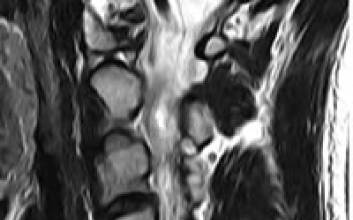

척추관 협착증이나 디스크가 심해지면 수술 이외의 치료법을 찾기 쉽지 않다. 수술은 절개를 해야 하고 뼈에 나사못을 박아 넣는 등 환자에게는 여간 부담이 아니다. 더구나 호전되기는 커녕 부작용이 나타나는 경우가 적지 않다. 그래서 물리치료나 침을 맞는 등 수술 없는 치료법에 관심이 높다. 특히 원리침은 시술 후 바로 움직일 수 있고 후유증도 거의 없어 주목받고 있다. 증상이 심각한 경우 한 번에 치료되지 않지만 수술과 달리 여러 번 받을 수 있다는 장점도 있다. 원리침 시술을 받는 환자들의 이야기를 들어봤다. 남극의 추운 날씨에 허리 협착증 증세가 심해졌던 오방석씨가 원리침 시술을 받고 회복하고 있다. 오른쪽 사진은 남극에서의 모습. 김진경 기자 # 사례1-오방석씨건설회사에 다니는 오방석(50)씨는 작년 11월말 남극 장보고 기지에 마감 공사 관리·감독을 하기 위해 갔다가 허리에 심한 통증을 느꼈다. 남극에 간 지 보름이 지나서 허리가 끊어지는 것 처럼 아프기 시작하더니 발까지 쥐가 났다. 의사가 있었지만 전문적인 치료를 받지 못하고 진통제를 먹고 버텼다. 남극이라서 제대로 된 치료를 받지 못하고 4개월 후 귀국해 일반 한의원에서 침을 맞았다. 당시에는 괜찮았는데 겨울이 되자 재발했다. 이번에는 재활병원에 갔지만 호전되지 않았고 수술을 받으라고 했다. 수술을 받으면 두 달에서 1년을 다녀야 한다고 했다. 그래서 처남댁이 수술 없이 치료를 받아 나아졌다는 원리침을 받아보기로 했다. MRI 촬영 결과 척추관이 좁아져 신경을 압박하는 허리 협착증은 심한 상태였고 목 디스크까지 와 있었다. 5일 간 입원해 두 부분에 대해 시술을 받았다. 끝이 둥근 원리침과 끝이 뾰족한 도침으로 신경을 누리고 있는 요인을 제거하는 시술을 이틀 간 받았다. 오씨는 시술을 받고 나서 통증이 많이 없어졌다고 했다. 허리와 목 통증은 거의 사라졌고 다리가 저리는 통증은 조금 남았다. 오씨는 "시술 후 걸어다니고 뛰지 말고 무거운 것을 들지 말라고 했는데 먹고 살아야 하니 다시 일을 시작해서인지 통증이 말끔히 없어지지 않았다"고 말했다. 하지만 오씨는 "아주 심한 경우 서너번을 받아야 좋아진다고 하고 후유증도 없다고 하니 한 번 더 받아볼 생각"이라고 말했다. # 사례2-박영순씨박영순(54)씨는 오래 전부터 허리 디스크로 고생한 환자다. 3년 전 허리가 좋지 않아 척추 전문 병원에서 얇은 주삿바늘을 디스크 안으로 삽입해 튀어 나온 디스크를 고주파로 융해시키는 고주파수핵감압술을 받았다. 하지만 전혀 효과가 없어서 한방병원에서 침이나 물리 치료를 받아왔다.그러나 근본적인 치료가 이뤄지지 않아 디스크는 더욱 심해졌다. 1년 전 부터는 오른쪽 엉치뼈부터 종아리, 발바닥까지 저리고 쑤셔서 직장을 다니는 것을 그만두고 좋아하던 산도 다닐 수 없게 됐다. 일상생활을 제대로 할 수 없는 지경이 된 것이다. 일반 병원에서는 수술 밖에 달리 방법이 없다고 했다. 박씨는 과거 실패한 경험이 있어 수술은 하고 싶지 않았다. 그래서 찾은 것이 수술 없이 시술하는 원리침이었다. 시술은 30분 가량으로 짧게 끝났으며 효과도 있었다. 심한 통증은 거의 사라졌고 저리고 쑤시는 잔통만 조금 남았다. 박씨는 "앉을 때 자세가 안좋으면 통증이 있긴 한데 바르게 펴고 있으면 괜찮다"고 말했다. 박씨는 디스크가 작아지고 공간이 생긴 것도 확인했다. 박씨는 "병원에서 치료를 받으면 MRI를 찍어서 호전됐는지 여부를 확인하는데 이번 원리침 시술 이후 MRI에서 튀어나온 디스크가 작아지고 공간도 생긴 것을 확인할 수 있었다"고 말했다. 박씨는 다만 "한 번 시술로 막힌 곳이 뻥 뚫리 듯 통증이 완전히 사라졌으면 했는데 그렇지는 않았다"며 "그래도 수술하는 것과 달리 몸에 크게 해가 되지 않는 것 같다"고 말했다. # 사례3-안영애씨73세로 고령인 안영애씨는 지난 9월부터 꼬리뼈에 통증을 느끼기 시작했다. 앉았다가 일어나려고 하면 까무러칠 정도로 아프고 조금한 상도 들 수가 없었다. 여기저기 동네에서 치료를 받았지만 나아지지 않았다. 수소문 끝에 원리침 시술을 받기로 했다. 허리 MRI 검사에서는 심각한 요추관 협착증 판단이 나왔다. 다행스럽게 영상에 비해 증상이 심하지 않은 초중기 단계였다. 그래도 안씨는 나이가 많아 원리침 시술의 효과가 있을지, 또 부작용은 없을지 걱정을 많이 했다. 반신반의로 끝이 둥근 원리침을 이용해 좁아진 척추관을 직접 뚫어주는 원리침 시술을 받았다. 그 결과 꼬리뼈 통증과 함께 다리의 약한 통증도 모두 사라졌다. MRI 상에는 심각한 상태였지만 증상이 심하지 않아 한 번의 원리침 시술로 통증이 모두 사라진 것이다. 안씨는 "나이가 많이 걱정을 많이 했는데 지금은 계단도 올라간다"며 "한 번의 시술로 통증이 깜쪽같이 없어져 신기할 뿐"이라고 말했다.권오용 기자 bandy@joongang.co.kr▶ 전문가 Q&AQ.겨울철에 협착증이나 디스크 통증이 심해지는 이유는.A.겨울에 기온이 떨어지면 혈관도 수축되면서 영양분이 잘 지나가지 못해 쥐가 나거나 근육이나 인대가 더 긴장하게 된다. 척추관 협착증이나 디스크는 혈관이 좁아지거나 디스크가 튀어나와 신경을 압박해 통증을 느끼는 것이기 때문에 추운 겨울에 평소 느끼지 못했거나 평소보다 더 심한 통증을 느끼게 된다. 도움말=이건목 대한한의침도학회장·세계침도학회부회장(http://www.drleeratoc.com) 2014.12.29 07:00